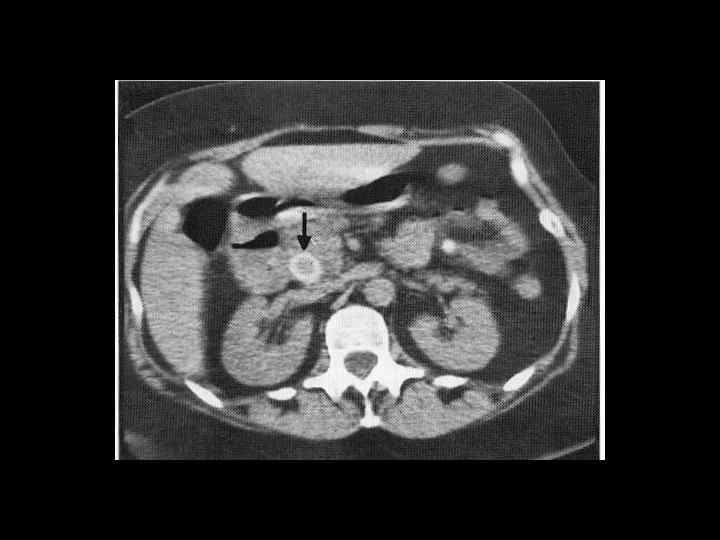

АКТУАЛЬНЫЕ ВОПРОСЫ РЕНТГЕНОЛОГИИ ЛУЧЕВАЯ ДИАГНОСТИКА ЗАБОЛЕВАНИЙ ЖЕЛЧЕВЫДЕЛИТЕЛЬНОЙ СИСТЕМЫ Желчекаменная болезнь КТ семиотика